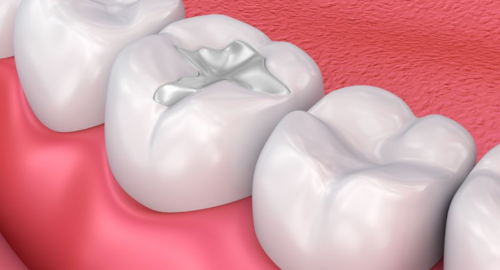

STEP 04

Final Restoration

A custom-fit porcelain crown is placed to fully restore the tooth's strength, function, and natural appearance, looking indistinguishable from your original tooth.